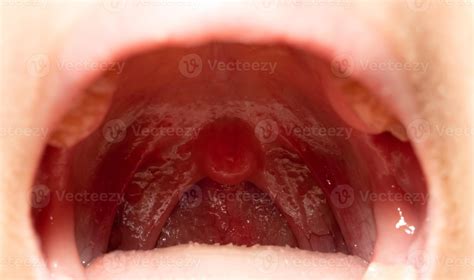

Have you ever experienced a sore on uvula? This small, fleshy piece of tissue that hangs down at the back of your throat can be quite bothersome when it becomes inflamed or irritated. A sore on uvula can cause discomfort, pain, and even difficulty swallowing. Understanding the causes, symptoms, and treatments for a sore on uvula can help you manage this condition effectively.

• Swelling: The uvula may appear swollen or enlarged.

• Redness: Inflammation and redness around the uvula.

• red sore on uvula

• canker sore on uvula picture